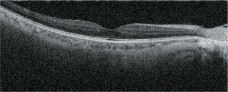

基于SLO的眼球追蹤功能

利用基于高清SLO的眼球追蹤功能實(shí)時(shí)補(bǔ)償眼球運(yùn)動(dòng),可實(shí)現(xiàn)更精確的掃描,確保更高的圖像質(zhì)量和盡可能的再現(xiàn)性。